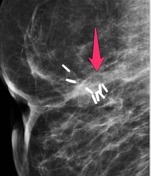

USS Case: Ultrasound demonstrates a solid, vascular mass within a cystic space, with clearly visualised intraductal extension. Appearance in keeping with a papillary lesion.